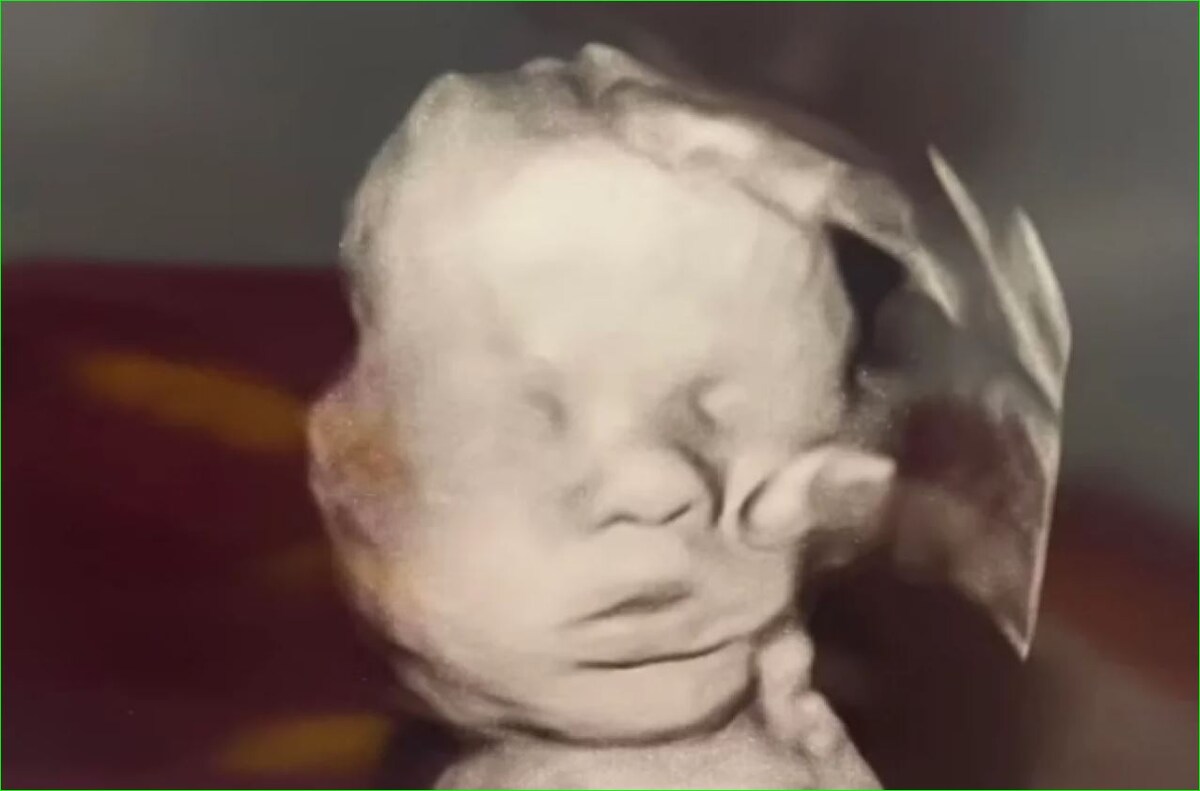

Гладящая ребенка «рука Бога» на снимке УЗИ беременной американки может быть пуповиной, сообщил aif.ru врач акушер-гинеколог-репродуктолог, кандидат медицинских наук Ринат Темирбулатов.

Врач Ринат Темирбулатов прокомментировал распространяемый в соцсетях снимок УЗИ, на котором, по словам беременной американки Аманды Фостер, видна "рука Бога", гладящая ее ребенка. Медик предположил, что загадочный объект может быть пуповиной, взвесью в околоплодных водах или артефактом ультразвукового исследования.

Ранее Daily Mail сообщила, что у ребенка Фостер, которая находится 32-й неделе беременности, диагностировали проблемы с сердцем. Женщина рассказала, что в молитвах просила Господа, чтобы он держал свою руку на моём ребёнке.

Аманда Фостер восприняла изображение УЗИ как Божественный знак.

"Интересно, увидят ли подобное на последующих УЗИ. Если нет, то это какой-то артефакт, скорее всего. Ультразвуковые лучи отражаются от чего-то, компьютер интерпретирует это и переводит отражение в картинку, которая в данном случае, конечно, красиво получилась",

приводит aif.ru мнение врача акушера-гинеколога-репродуктолога, кандидата медицинских наук Рината Темирбулатова.

Снимок уже стал вирусным, вызвав многочисленные дискуссии в сети: некоторые пользователи верят вместе с будущей мамой в чудо, другие называют его оптическим искажением. Ранее протоиерей Русской Православной Церкви Константин Харитонов прокомментировал появление образа Божией Матери в хирургическом центре в Центральном военном клиническом госпитале имени А.А. Вишневского в Красногорске.